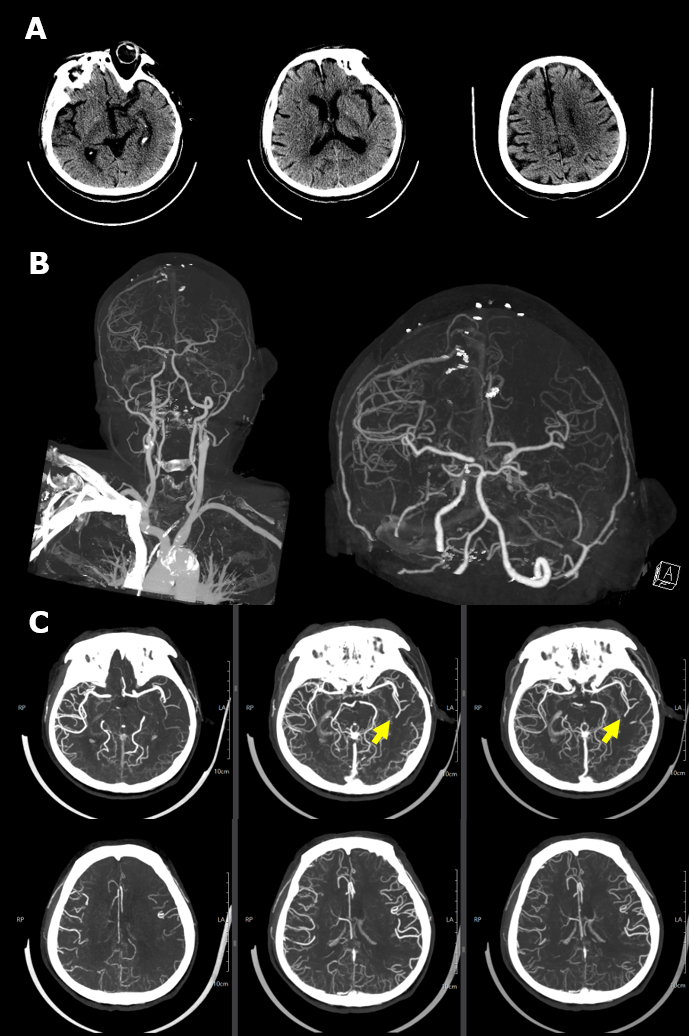

An 84-year-old male was transferred from another hospital for decreased mentality with right hemiparesis. He had visited the hospital for chest pain. While waiting for examination, he suddenly collapsed with desaturation and was transferred for proper management. Computed tomography angiography showed left proximal ICA occlusion and the left anterior cerebral artery with the left middle cerebral artery supplied via the anterior communicating artery. Electrocardiography indicated anterior wall ST elevation myocardial infarction (STEMI). Portable echocardiography findings suggested left anterior descending (LAD) artery territory insult. After a discussion with the attending cardiologist, we decided on intervention for STEMI first. After loading dual antiplatelet agents, PCI was done. After the procedure, we did EVT on the left ICA. The first pass effect was achieved by aspiration thrombectomy.